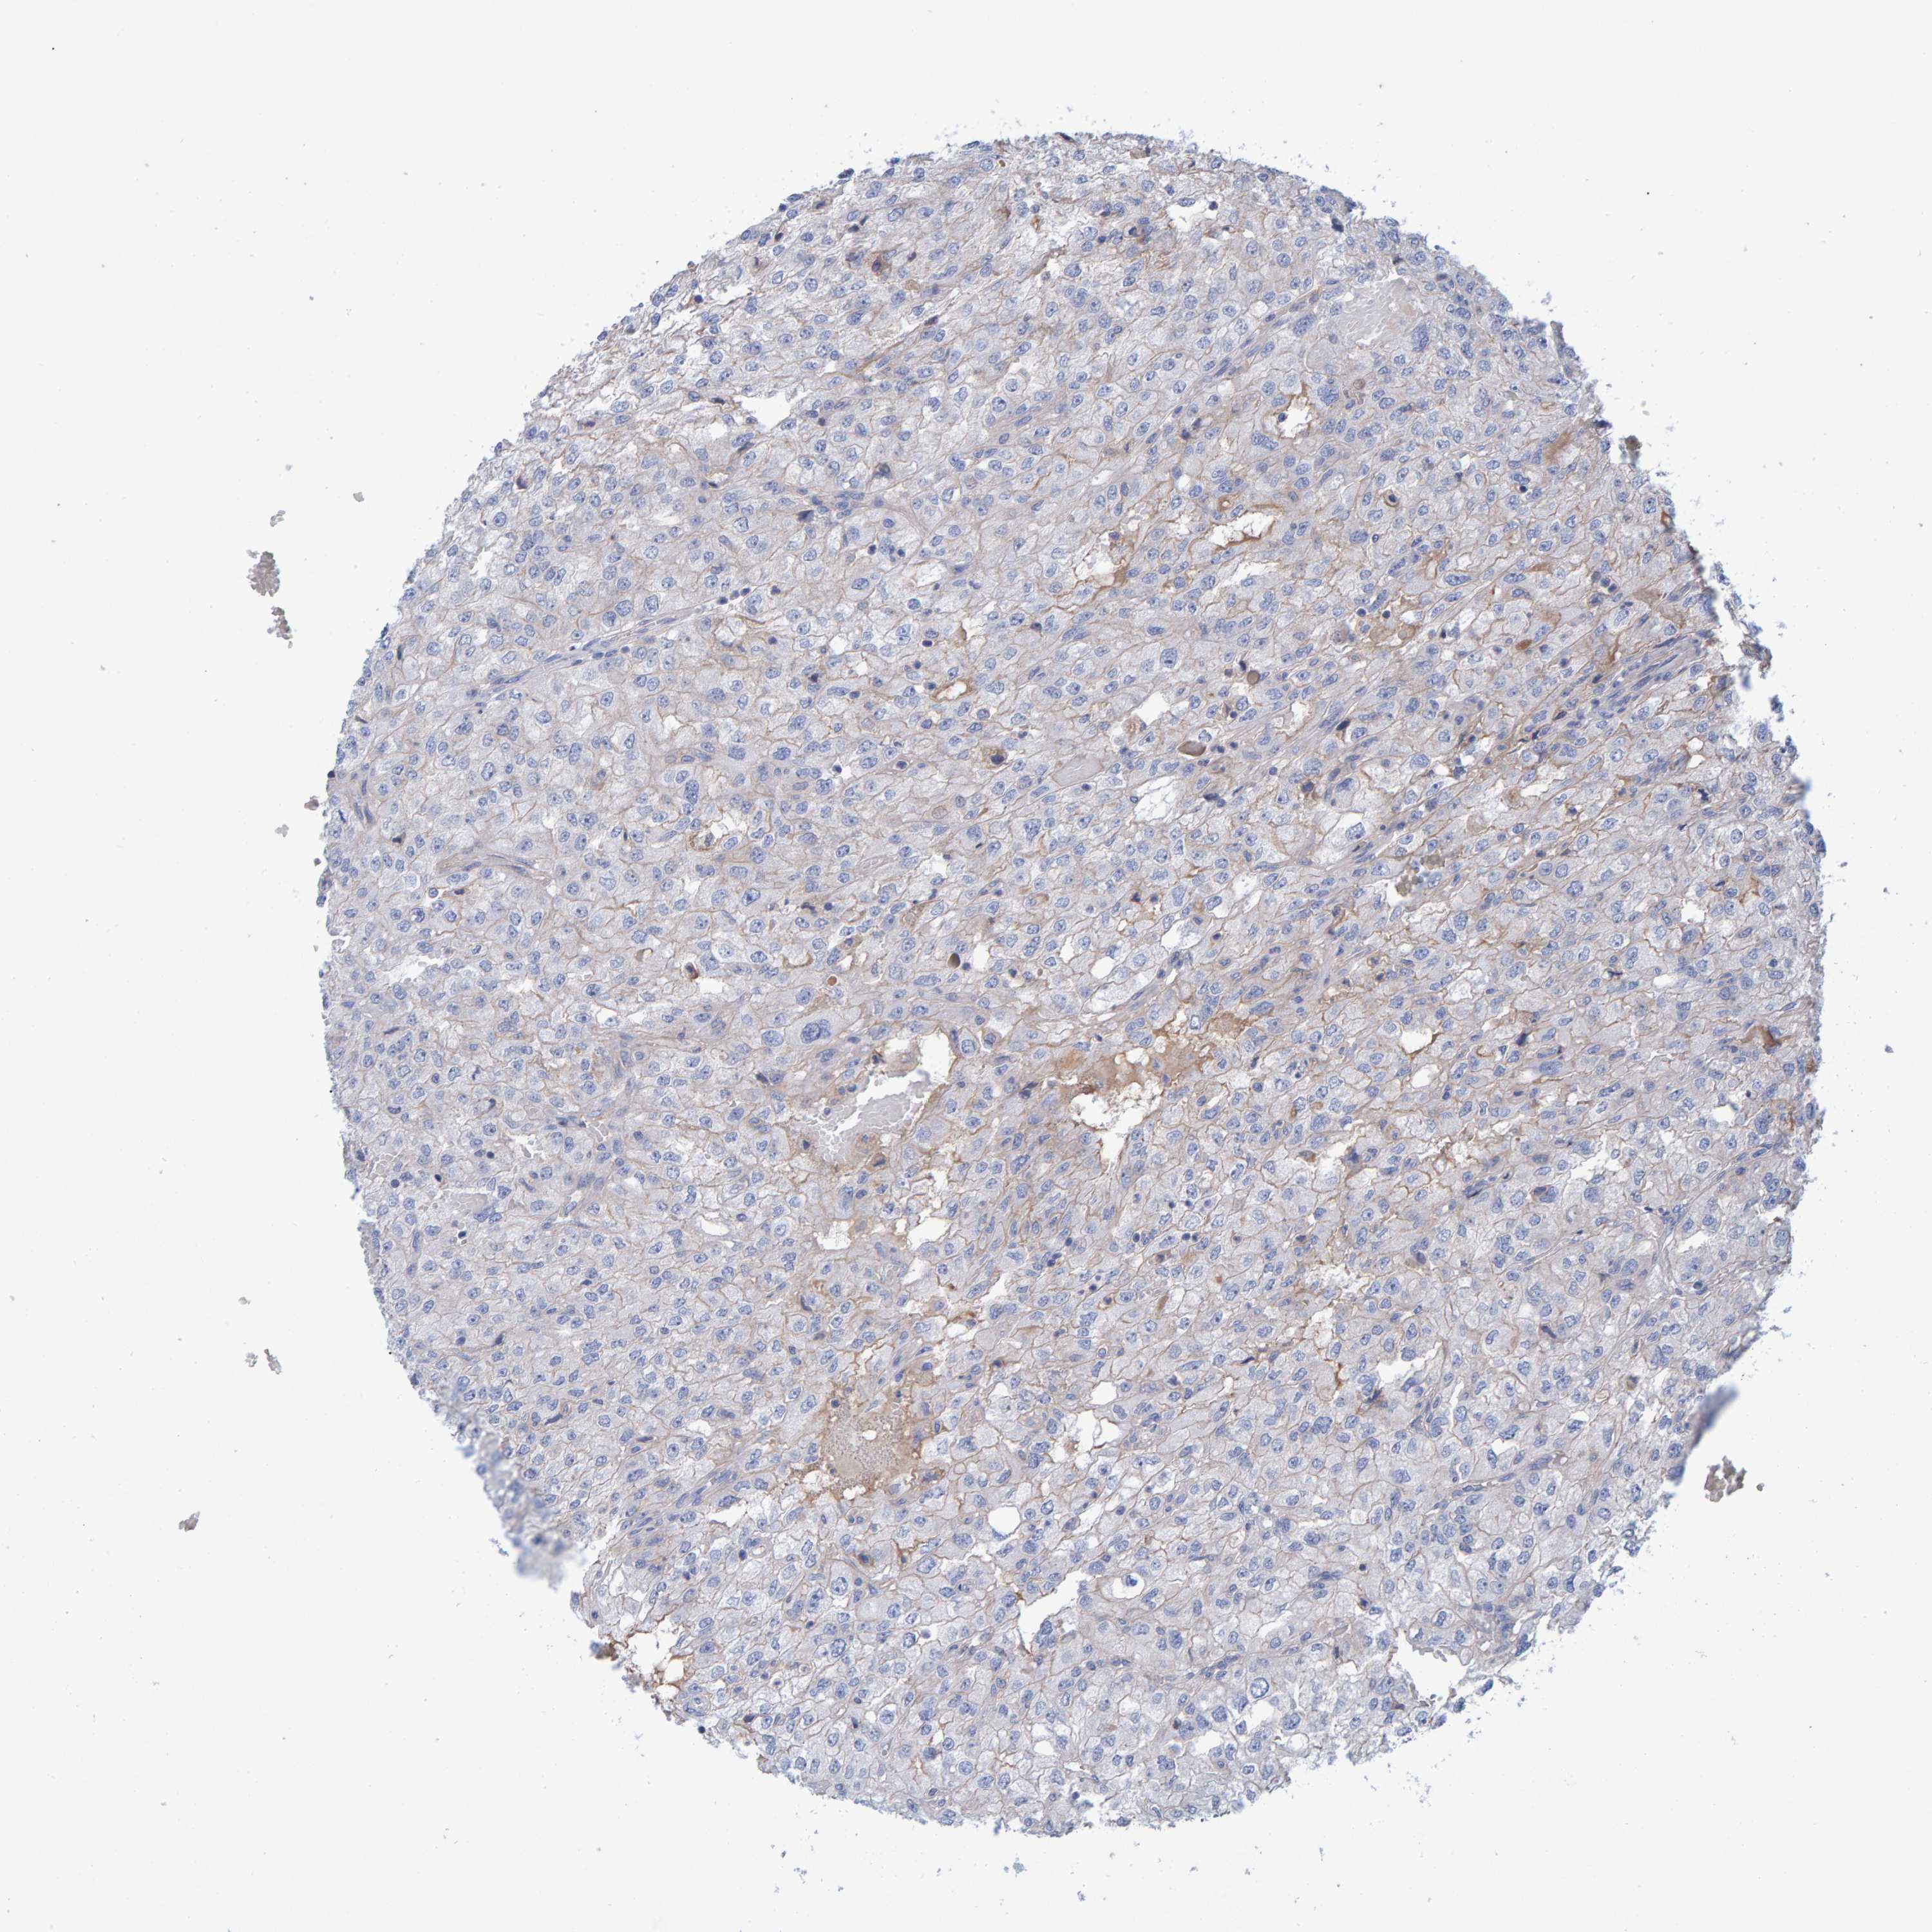

KIDNEY RENAL PAPILLARY CELL CARCINOMA (TCGA) - Interactive survival scatter ploti

The Survival Scatter plot shows the clinical status (i.e. dead or alive) for all individuals in the patient cohort, based on the same data that underlies the corresponding Kaplan-Meier plots. Patients that are alive at last time for follow-up are shown in blue and patients who have died during the study are shown in red.

The x-axis shows the expression levels (FPKM) of the investigated gene in the tumor tissue at the time of diagnosis. The y-axis shows the follow-up time after diagnosis (years). Both axes are complimented with kernel density curves demonstrating the data density over the axes. The top density plot shows the expression levels (FPKM) distribution among dead (red) and alive patients (blue). The right density plot shows the data density of the survived years of dead patients with high and low expression levels respectively, stratified using the cutoff indicated by the vertical dashed line through the Survival Scatter plot. This cutoff is automatically defined based on the FPKM cutoff that minimizes the p-score. The cutoff can be changed by dragging the vertical line or by entering a cutoff value in the square labeled "Current cut-off".

Under the Survival Scatter plot the p-score landscape (black curve; left axis) is shown together with dead median separation (red curve; right axis). Dead median separation is the difference in median mRNA expression between patients who have died with high and low expression, respectively. It is calculated as follows: median FPKM expression of dead patients with high expression - median FPKM expression of dead patients with low expression. This is intended to aid the user in visually exploring custom cutoffs and the associated p-scores and dead median separation.

Individual patient data is displayed and can be filtered by clicking on one or more of the category buttons on the top of the page. Categories describing expression level and patient information include: high, low, alive, dead, female, male and tumor stages. The scale of the x-axis can be toggled between linear and log-scale by clicking on the "x log" button. Mouse-over function shows TCGA ID, patient information and mRNA expression (FPKM) for each patient.

& Survival analysisi

Kaplan-Meier plots summarize results from analysis of correlation between mRNA expression level and patient survival. Patients were divided based on level of expression into one of the two groups "low" (under cut off) or "high" (over cut off). X-axis shows time for survival (years) and y-axis shows the probability of survival, where 1.0 corresponds to 100 percent.

EFR3A is not prognostic in Kidney Renal Papillary Cell Carcinoma (TCGA)

Best expression cut offi

Based on the FPKM value of each gene, patients were classified into two groups and association between prognosis (survival) and gene expression (FPKM) was examined. The best expression cut-off refers the FPKM value that yields maximal difference with regard to survival between the two groups at the lowest log-rank P-value. Best expression cut-off was selected based on survival analysis .

When clicking on this number, the vertical dashed line indicating cut-off, the interactive survival plot, and the Kaplan-Meier curve will be adjusted to show results based on the best expression cut-off.

: 24.12